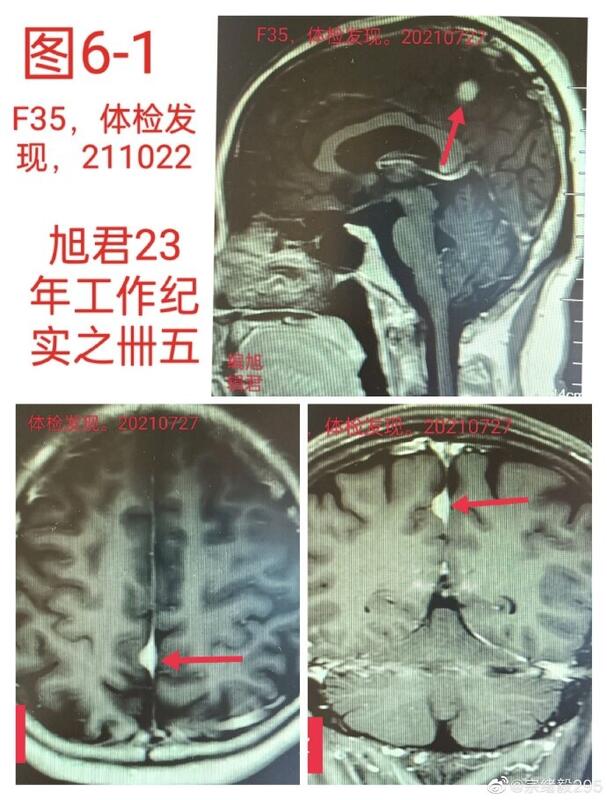

图6,1-2:某患者35岁,体检发现,观察一年复查无变化,无不适。

图6-1

图6-2